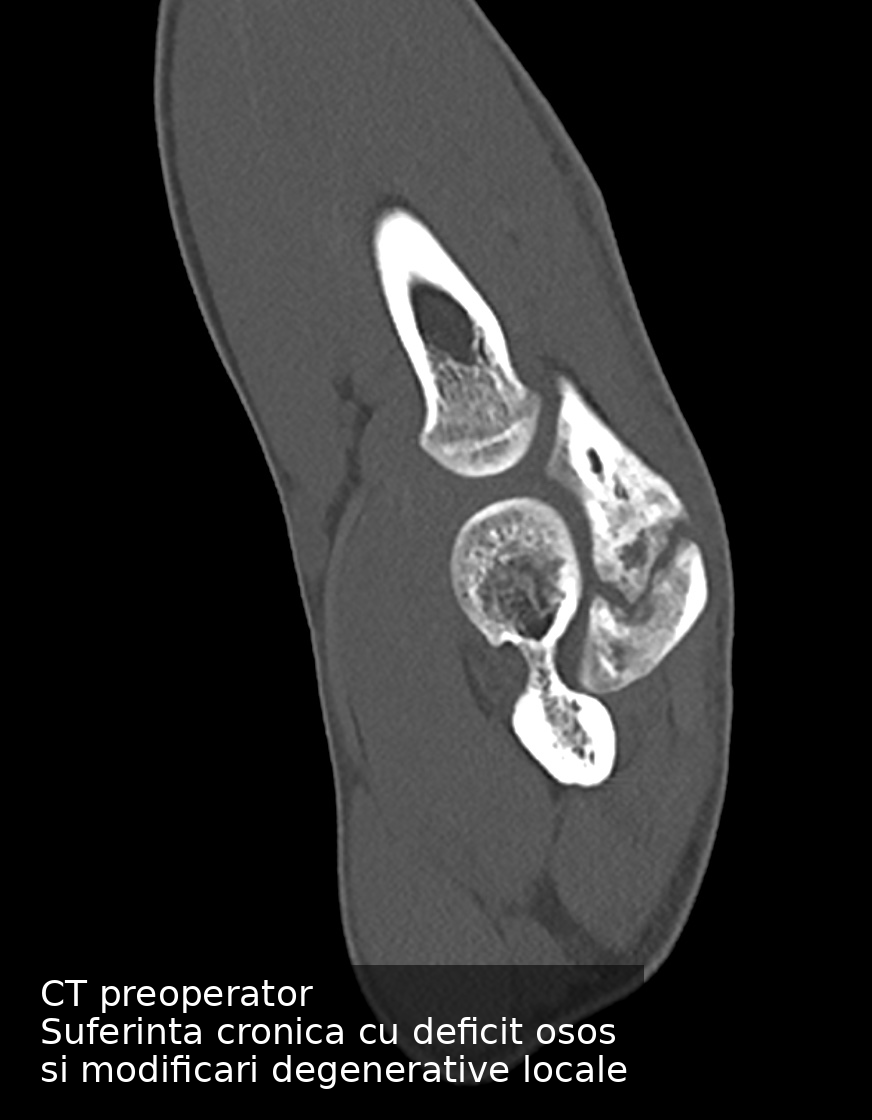

Pacientul a trecut printr-o suferință prelungită de aproape un an, perioadă în care durerile au progresat, iar forța la nivelul cotului a scăzut treptat. Sportivii sunt obișnuiți să funcționeze cu durere, iar în acest caz activitatea competițională a fost continuată în ciuda degradării progresive a funcției. La momentul primei evaluări, situația ajunsese într-un stadiu avansat. Traumatismele repetate specifice judo-ului au împiedicat maturizarea cartilajului de creștere în os, apofiza olecraniană rămânând separată de restul ulnei, cu apariția unui deficit osos vizibil radiologic.

Provocarea principală a fost reprezentată de deficitul osos asociat și de riscul unei fixări rigide clasice, care ar fi presupus aproape sigur o a doua intervenție pentru îndepărtarea materialului de osteosinteză. Pentru un atlet activ în competiții internaționale, acest lucru înseamnă nu doar timp pierdut, ci și un risc suplimentar pentru cot pe termen lung.